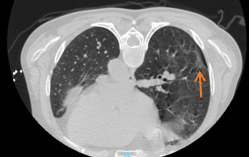

唐中明主任带领团队认真研究,细心评估,考虑:1.右下肺磨玻璃结节随访10月仍存在,2.影像学提示右下肺磨玻璃结节有血管支配供血,虽然结节较小,但仍属于高危结节;3.患者心理负担重,4.患者左上肺腺癌根治术术后,综合考虑要解决右下肺磨玻璃结节首选微波消融术,胸外科一病区团队量身定制了微波消融治疗方案。3月28日,唐中明主任在CT引导下,将一根直径不到2mm的消融针经皮肤精准刺入患者肺部结节病灶内行微波消融术,术后患者皮肤仅留有一细小针眼,患者术后2小时下床活动、正常进食。在胸外科一病区加速康复的照护下,患者恢复良好。

▲消融后肺结节消失